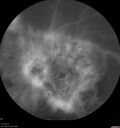

Branch Retinal Vein Occlusion - Both Eyes - Edema OD and NVE OS - Severe Non-perfusion Both Eyes324 views83 year old man with vision loss for 3 months not sure which eye. VA 20/100 OD and 20/50 OS. Tried avastin once without much improvement in the right eye and then lost to follow-up. FA in the left eye shows leaking NVENov 30, 2020

|

Branch Retinal Vein Occlusion - Both Eyes - Edema OD and NVE OS - Severe Non-perfusion Both Eyes369 views83 year old man with vision loss for 3 months not sure which eye. VA 20/100 OD and 20/50 OS. Tried avastin once without much improvement in the right eye and then lost to follow-up. FA in the left eye shows leaking NVENov 30, 2020